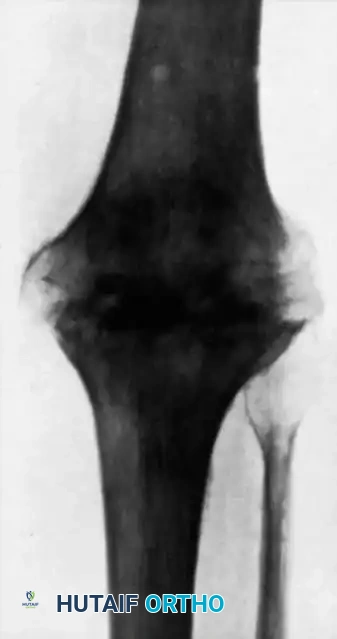

The Knee

The knee is the most commonly affected appendicular joint. Patients present with a boggy, swollen joint, severe quadriceps atrophy, and a flexion contracture.

If diagnosed early (synovial stage), arthroscopic synovectomy combined with chemotherapy can preserve joint function. However, once the subchondral bone is compromised and the articular cartilage is destroyed (as demonstrated in the radiograph above), joint preservation is no longer viable.